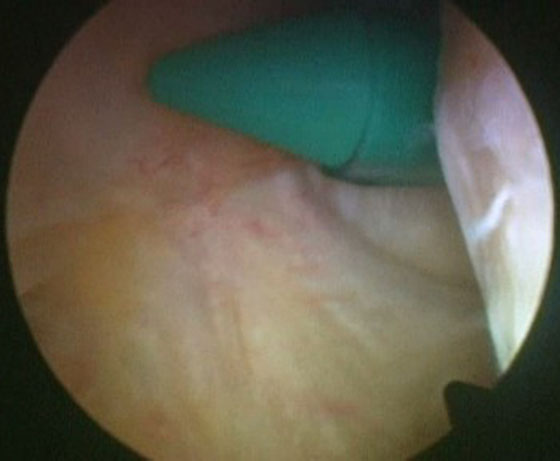

Se insufla el manguito neumático y se comienza la artroscopia por los portales anteromedial y anterolateral, se reconoce la lesión, se solucionan lesiones asociadas (meniscales, condrales, cuerpos libres) y se pasa a realizar el túnel femoral. Se localiza la hora 12 del intercóndilo, se visualiza la tróclea femoral y se ubica el sitio del túnel femoral (hora 1 rodilla derecha, hora 11 rodilla izquierda) (Fig. 2). Este túnel debe estar lo más alto posible en el intercondilo para colocar un injerto bien “vertical”. Realizamos este paso primero, haciendo el túnel desde el portal anterolateral, para evitar la dificultad de realizarlo después de la liberación capsular posterior que nos dejará menor cantidad de líquido intraarticular, y consecuentemente menor distensión dificultando la visión. Identificado el sitio de inserción, y sin resecar las fibras remanentes se coloca la fresa del diámetro a utilizar de manera de buscar que queden unos 3 mm desde la parte periférica proximal de la fresa hasta el cartílago articular del fémur, se pasa a través de la fresa canulada un clavo guía, se retira la fresa para confirmar la ubicación y se realiza el túnel de 20 o 25 mm de largo, de acuerdo al tipo de injerto que utilicemos. A continuación se ubica el espacio entre las fibras remanentes del LCP y el LCA, se debrida con shaver para dejar permeable este espacio, que nos permitirá más tarde traer el injerto desde la inserción tibial hacia la parte anterior de la rodilla (Fig. 3).

Figura 2

Figura 3